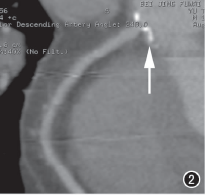

图2 右冠状动脉开口部可见钙化,管腔局限性重度狭窄(箭)。